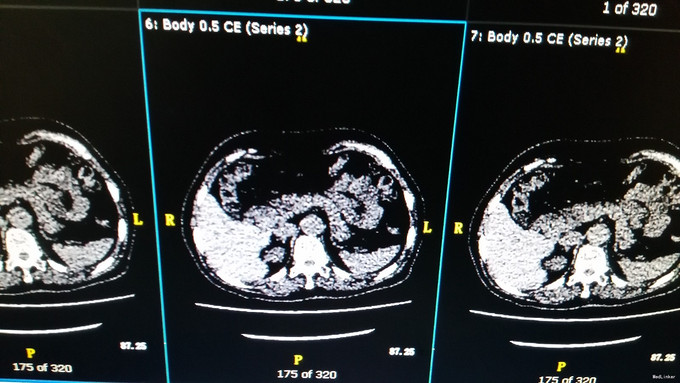

体格检查:神志清楚,表情较淡漠,反应迟钝,能正确回答问题。毛发稀疏,腋毛、阴毛脱落,眉毛稀疏。 入院后完善相关检查: 皮质醇节律: 8:00 15:00 24:00 COR(nmol/L): 455.8 232.9 102.0 ACTH(pg/ml): 10.92 11.21 6.69 糖耐量-胰岛功能测定: 0分 30分 60分 120分 180分 240分 300分 葡萄糖(mmol/L) : 4.84 8.52 7.82 5.70 9.28 6.15 5.30 C肽(pmol/L): 757.45 3327.86 4465.4 2382.0 2521.14 1513.0 胰岛素(mIU/L): 10.28 106.90 112.6 17.07 64.58 21.62 9.87 胰岛素原(pg/ml): 185.28 406.38 678.25 608.88 697.69 639.78 糖尿病抗体系列:血清抗胰岛素自身抗体测定IAA 6.57IU/mL,血清抗谷氨酸脱羧酶抗体测定GAD 8.89IU/mL。 饥饿试验 血糖:4.05mmol/L 胰岛素:5.73mIU/L C肽:286.14pmol/L 胰岛素原:163.21pg/mL 胰岛素释放指数:胰岛素/血糖÷18=0.078 胰腺CT灌注(64排):胆道低位梗阻,梗阻于胆总管胰段,邻近管壁增厚.

患者饥饿试验时胰岛素、C肽、胰岛素原、胰岛素释放指数均未明显升高,未出现低血糖发作症状,目前不支持胰岛细胞瘤的诊断。以上化验\试验及影像学不支持胰岛素瘤的诊断.建议继续完善MRCP等检查明确胆道梗阻病因,但家属要求出院回当地医院继续检查.